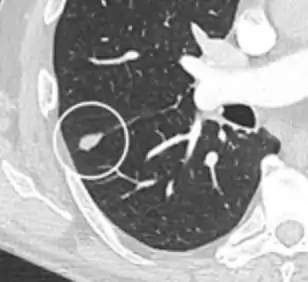

Lung nodule abutting a pulmonary cyst.[9]

• A lung nodule abutting a pulmonary cyst is a rare finding, yet indicating cancer.[9]

Thin slice and maximal intensity projection of a lung nodule, the latter better visualizing vascular convergence.[9]

• Vascular convergence is where vessels converge to a nodule without adjoining or contacting the edge of the nodule, and is mainly seen in peripheral subsolid lung cancers.[9] It reflects angiogenesis.[9]